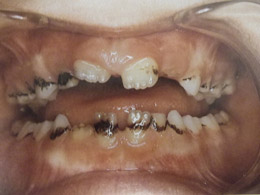

Τερηδόνα βρεφικής και νηπιακής ηλικίας ή τερηδόνα θηλασμού

Η τερηδόνα βρεφικής και νηπιακής ηλικίας εμφανίζεται σε μικρά παιδιά ηλικίας 2 έως 5 ετών, τα οποία έχουν τερηδονισμένα ένα ή και περισσότερα νεογιλά δόντια. Η τερηδόνα αυτής της μορφής οφείλεται σε λάθος τρόπο διατροφής του παιδιού και μπορεί να εξελιχθεί γρήγορα και σε μεγάλη έκταση επηρεάζοντας το σύνολο το δοντιών που βρίσκονται στο στόμα.

Η κυριότερη αιτία εμφάνισης της τερηδόνας αυτής της μορφής είναι το τάισμα με το μπιμπερό ενώ το παιδί κοιμάται. Κατά τη διάρκεια του ύπνου η ποσότητα του σάλιου μειώνεται και το γάλα, ανεξάρτητα αν περιέχει ή όχι ζάχαρη, παραμένει πάνω στα δόντια και προκαλεί τερηδόνα. Ακόμη και το μητρικό γάλα μπορεί να έχει τις ίδιες συνέπειες, εφόσον το παιδί θηλάζει κατά βούληση κατά τη διάρκεια της νύχτας.

- Η τερηδόνα των νεογιλών δοντιών προκαλεί πόνο και μερικές φορές πυρετό και κακουχία στο παιδί, καταστάσεις δυσάρεστες τις οποίες κανένας γονιός δεν θα ήθελε να βιώσει το παιδί του.

- Η παρουσία τερηδονισμένων νεογιλών δοντιών μπορεί να επηρεάσει και τα μόνιμα δόντια, διότι η τερηδόνα οφείλεται στα μικρόβια τα οποία μεταδίδονται με το σάλιο από δόντι σε δόντι. Εφόσον το περιβάλλον της στοματικής κοιλότητας που αναπτύσσονται τα μόνιμα δόντια δεν είναι υγιές, τότε είναι θέμα χρόνου να "χαλάσουν" και αυτά.